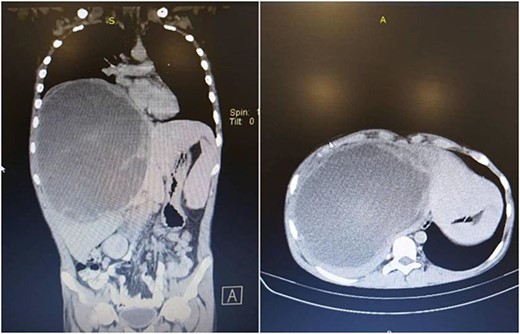

The patient underwent an ultrasound-guided fine needle aspiration. Histopathological examination of the tumor cells displayed pleomorphic cells with a high n/v ratio consistent with mesenchymal origin. Immunohistochemical expression showed positivity for desmin and vimentin and negativity for hep par and CD 138 (Fig. 3).

The diagnosis was embryonal rhabdomyosarcoma based on the immunohistochemical result.